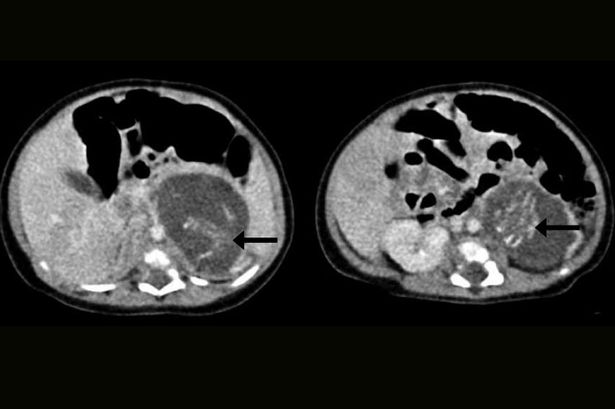

Bebê nasceu grávido de gêmeos e surpreendeu médicos na China, passando por cirurgia de remoção dos fetos com apenas três semanas de gestação.

A condição, conhecida como “foetus in foetu”, ocorre apenas em um de 500.000 nascimentos no mundo.